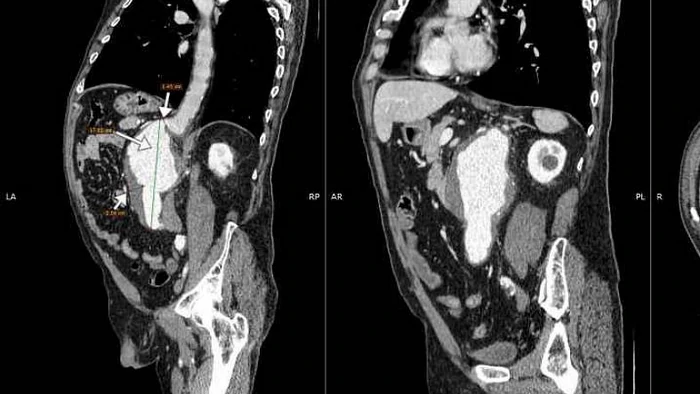

Картина напоминает 3D-модель. Можно измерить диаметр аорты буквально до миллиметра.

Аневризма выглядит как «вздутие». Это похоже на тонкое место в стенке садового шланга. Расслаивание — это «двойной ход» крови в стенке сосуда. Также видно кальцинаты, язвы бляшек, пристеночные тромбы. Поэтому врач чётко понимает, где опасность и как действовать.